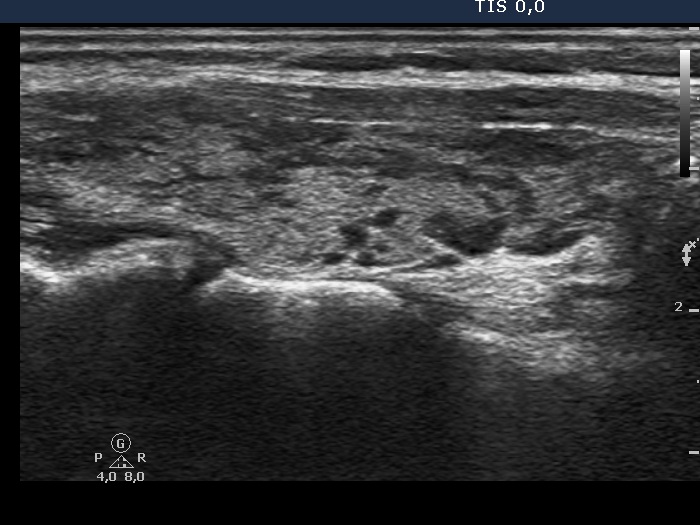

The thyroid gland is located in the neck, just above where your collarbones meet in the middle. Web chronic thyroiditis is caused by a reaction of the immune system against the thyroid gland. The disorder is also called hashimoto disease.

These antibodies cause inflammation in your thyroid gland. This disorder can be either painful or not felt at all. The thyroid gland is located in the neck, just above where your collarbones meet in the middle.

Web chronic thyroiditis is caused by a reaction of the immune system against the thyroid gland. The number of people who have hashimoto’s disease in the united states is unknown. There are four main types of thyroiditis:

Web hashimoto’s thyroiditis, also known as hashimoto’s disease, damages your thyroid function. Web hashimoto’s thyroiditis is also known as chronic lymphocytic thyroiditis or autoimmune thyroiditis. However, the disease is the most common cause of hypothyroidism, which affects about.

This means you develop antibodies [thyroid peroxidase (tpo) and/or thyroglobulin (tg) antibodies] that damage your thyroid gland. The disorder is also called hashimoto disease. The thyroid gland is located in the neck, just above where your collarbones meet in the middle.

This can last for a few weeks or months. Subacute thyroiditis is believed to be triggered by a viral infection. It often results in reduced thyroid function ( hypothyroidism ).